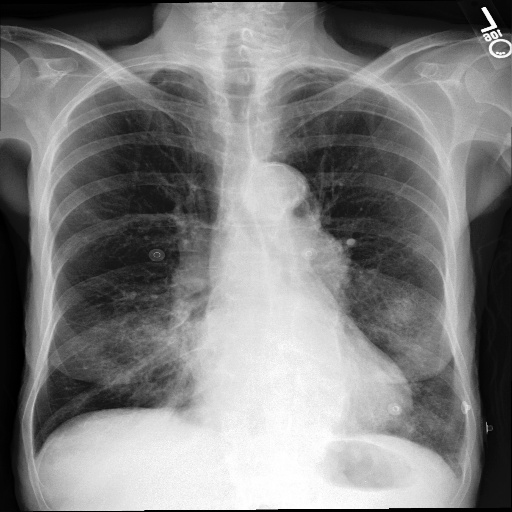

To assess whether dataset-specific signals are present in images independent of pathology, we train a 4-way classifier to predict dataset source (MIMIC-CXR, CheXpert, ChestX-ray14, PadChest). We use DenseNet-161, which achieved the highest internal AUROC and AUPRC in three of the four datasets in our domain shift analysis. Using the strongest-performing architecture ensures that any ability to distinguish dataset sources reflects genuine learnable signatures rather than limitations of model capacity. This DenseNet-161 backbone is trained from scratch on our four training datasets, using only pixel data. Performance is evaluated using Sensitivity, Specificity and F1-Score for each of the four classes (source datasets). As chance-level accuracy is 25%, substantially higher performance would indicate that non-pathological features (e.g., text markers, intensity scaling, acquisition artefacts) allow models to distinguish datasets. Results are shown in Table 5. Example images from each source dataset are shown in Figure 5.

The DenseNet-161 dataset-source classifier achieved near-perfect performance across all four classes (source datasets), far exceeding the 25% chance level. This indicates that public chest radiography datasets contain strong, easily learnable site-specific signatures. which are deeply embedded in the data. These signals are unrelated to pathology and instead likely reflect differences in acquisition protocols, scanner hardware, image post-processing pipelines, or embedded text markers. This finding highlights a critical shortcoming of current public benchmarks - models may exploit non-clinical cues that distinguish datasets rather than learning generalisable representations of disease.

Refer to caption

(a) CheXpert

(b) MIMIC-CXR

(c) ChestX-ray14

(d) PadChest

(e) CheXpert

(f) MIMIC-CXR

(g) ChestX-ray14

(h) PadChest

Figure 5: Example chest radiographs from MIMIC-CXR, CheXpert, ChestX-ray14 and PadChest. Each image contains text artefacts.